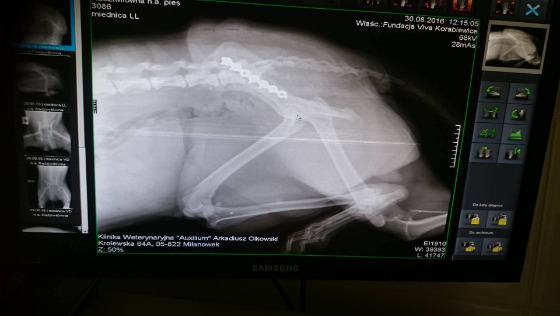

Potrącona sunia, zabrana przez nas z ulicy z Radziwiłowa (miejscowość niedaleko nas). Zawieźliśmy do zew. kliniki w Milanówku, gdzie leczymy nasze najcięższe przypadki. Badanie rtg wykazało złamanie miednicy. Koszt operacji i hospitalizacji to 2000zł.

To drugi psiak po Bursztynie, którego przyjęliśmy w ostatnim czasie pod opiekę po ciężkim złamaniu. Bursztyn przeszedł operację i zaczyna używać złamanej kończyny, przebywa w DT w Warszawie. Teraz czas na nowe życie suni. I czas znów na żebranie o pieniądze.